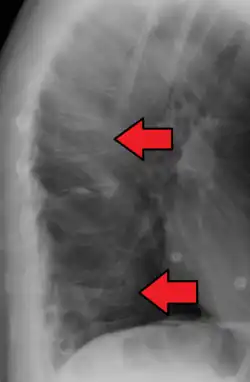

Compression fracture of T12

A compression fracture is a collapse of a vertebra. It may be due to trauma or due to a weakening of the vertebra (compare with burst fracture). This weakening is seen in patients with osteoporosis or osteogenesis imperfecta, lytic lesions from metastatic or primary tumors,[1] or infection.[2] In healthy patients, it is most often seen in individuals suffering extreme vertical shocks, such as ejecting from an ejection seat. Seen in lateral views in plain x-ray films, compression fractures of the spine characteristically appear as wedge deformities, with greater loss of height anteriorly than posteriorly and intact pedicles in the anteroposterior view.[3]